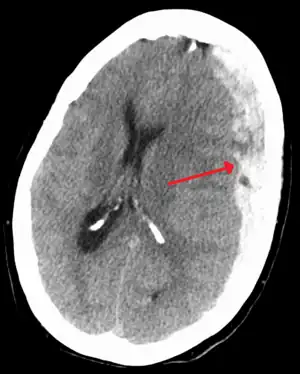

Subdural hematoma as marked by the arrow with significant midline shift

A subdural hematoma (SDH) is when a collection of blood forms between the inner layer of the dura mater and the arachnoid mater of the meninges surrounding the brain.[2] Symptoms may include headache, confusion, personality change, and loss of consciousness.[1] Complications may include brain herniation and seizures.[2]